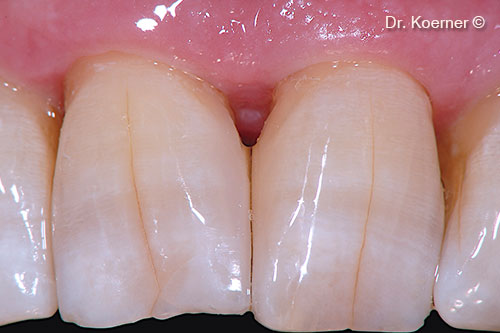

Initial situation

A male patient (61 years old) shows a periodontal defect in the esthetic area

Localized periodontal defect 11